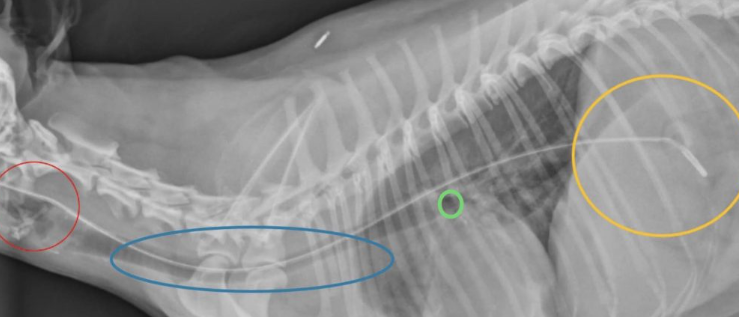

일명 콧줄이라고 하는 비식도관, 비위관 장착에 있어 많은 수의사들이 오랫동안 논쟁을 한 주제가 있다.

삽입한 튜브의 끝단이 식도에 위치하는 게 좋은가, 이내에 위치하는 게 좋은가에 대한 논쟁이다. 이 부분에 대한 정리를 해주는 논문이 나와 소개한다.